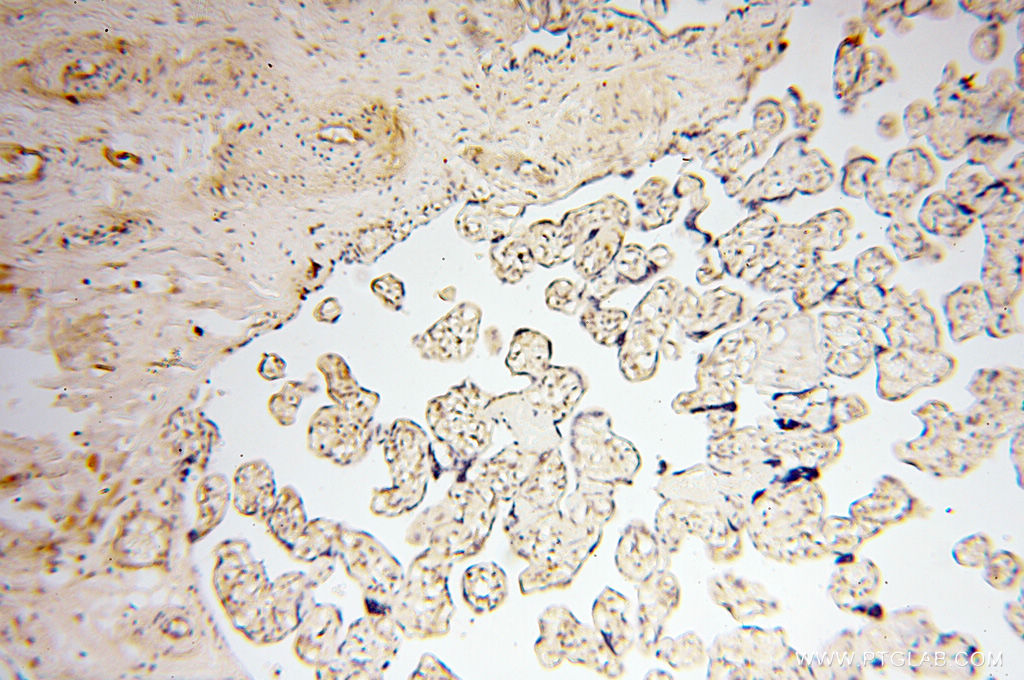

| Positive IHC detected in | human colon cancer tissue, human placenta tissue, human tonsillitis tissue, human testis tissue Note: suggested antigen retrieval with TE buffer pH 9.0; (*) Alternatively, antigen retrieval may be performed with citrate buffer pH 6.0 |

| Immunohistochemistry (IHC) | IHC : 1:50-1:500 |